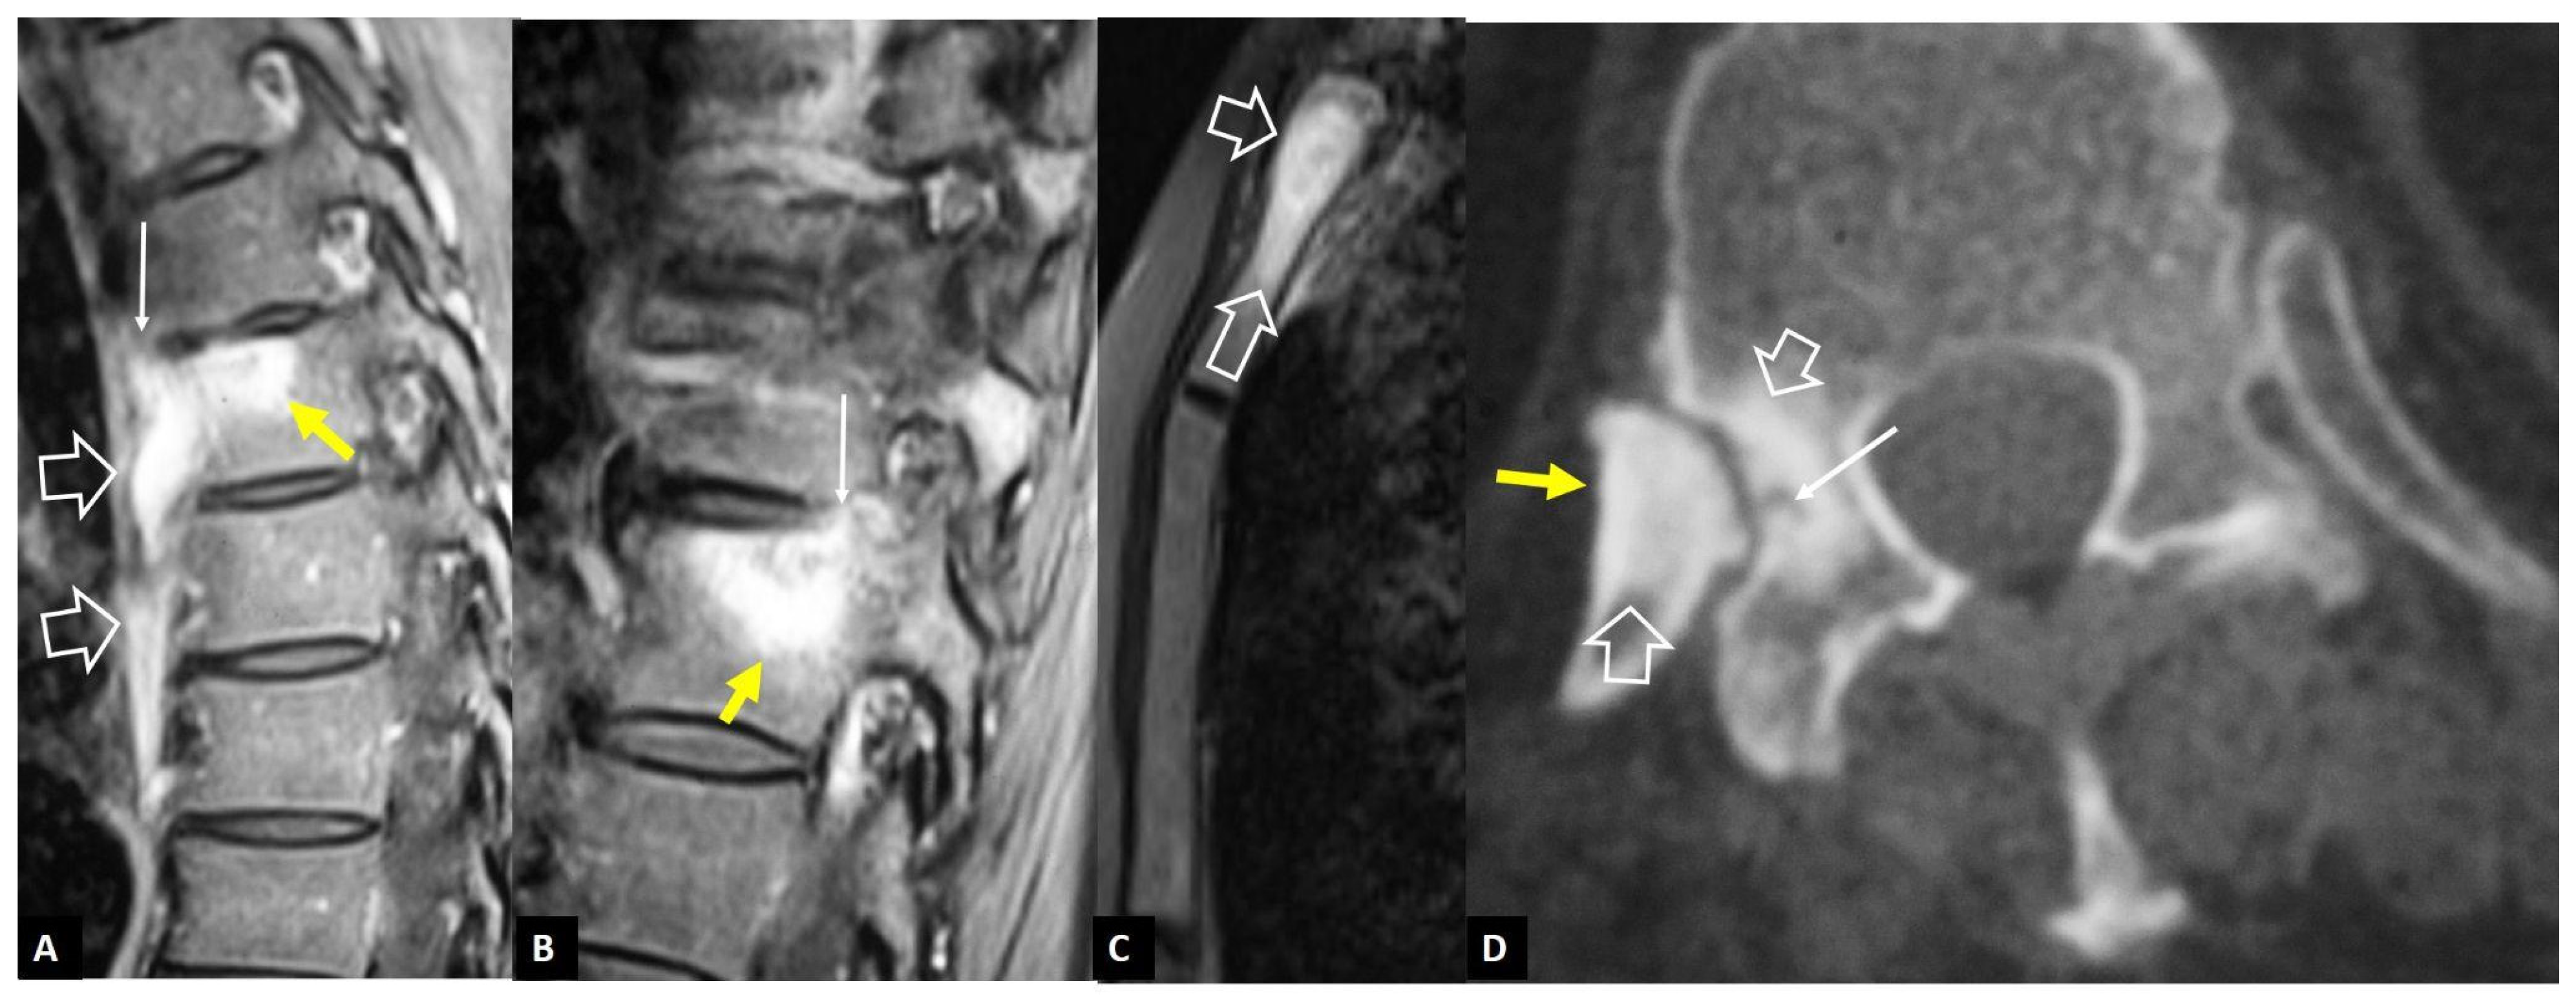

2.1.2. Aseptic Spondylodiscitis

2.1.3. SAPHO Syndrome

2.1.4. Destructive Spondyloarthropathy

2.1.5. Crystal Deposition

2.1.6. Post-Operative Aseptic Discitis

2.1.7. Trauma